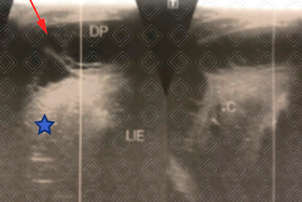

Texto alternativo para a imagem Figura 4. Créditos: Dra. Elazir Mota - Rio de Janeiro/RJ

Descrição das figuras 3 e 4: Ultrassonografia do hemitórax esquerdo evidenciando a consolidação homogênea com broncograma aéreo de permeio (asteriscos) e o derrame pleural (setas vermelhas). No caso do paciente em questão, trata-se de um derrame na fase fibrinopurulenta, pois observam-se alguns septos móveis no interior do derrame.

• Fase fibrinopurulenta (evolução de 2 a 10 dias): Caso a antibioticoterapia não seja adequada ou ineficaz, as bactérias que originaram a própria pneumonia tendem a invadir o líquido pleural e começam a acumular restos de células, leucócitos e bactérias. Inicia-se assim produção de fibrina, que acarreta no surgimento de septos, grumos e debris no interior do derrame pleural e na loculação. A loculação previne a disseminação do processo. Nesta fase, a abordagem cirúrgica se faz necessária para desfazer os septos e as lojas, permitindo a reexpansão adequada do pulmão;

• Ultrassonografia de tórax: Permite a graduação do derrame em leve, moderado ou acentuado e, além disso, auxilia na caracterização do derrame em exsudato, fase fibrinopurulenta ou organizada, ajudando na tomada de decisão pela equipe pediátrica e cirurgia pediátrica. Deste modo, é uma ferramenta auxiliar à radiografia do tórax na população pediátrica;